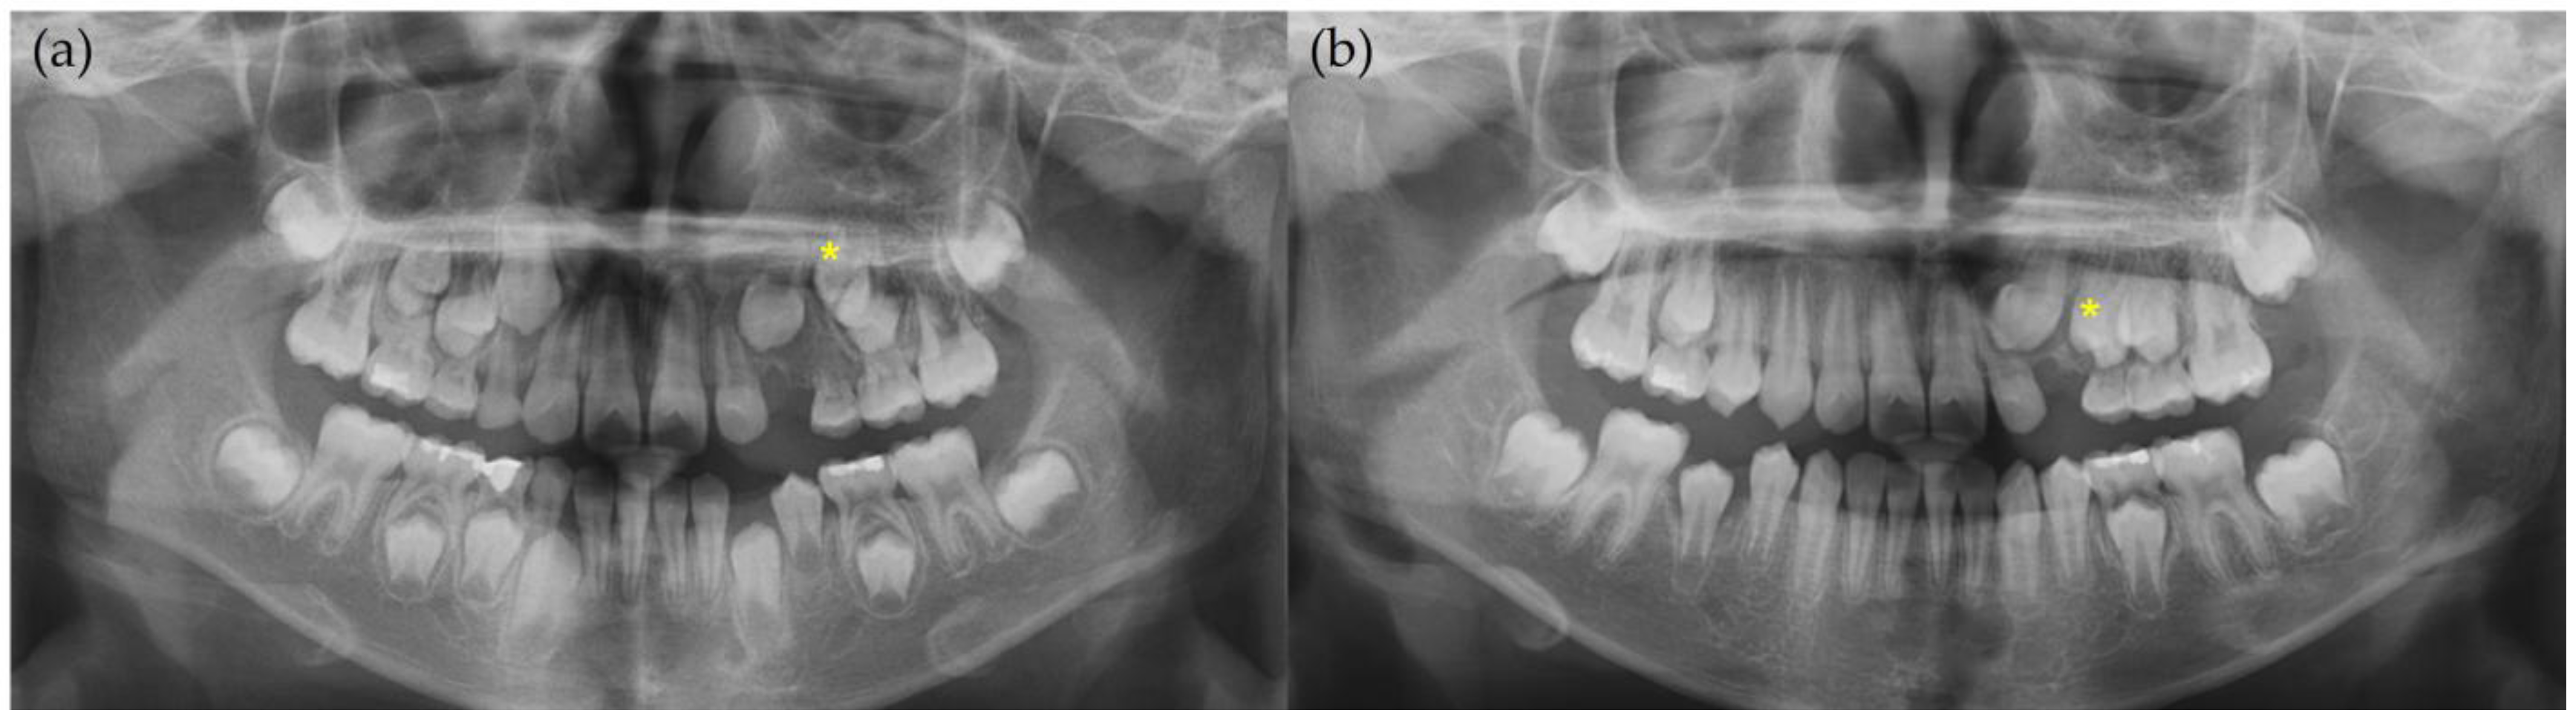

2. Case Report